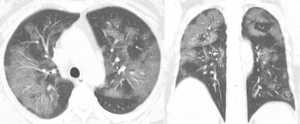

Άλλες σαρώσεις μιας 54χρονης γυναίκας που προσβλήθηκε από τον κορονοϊό μετά από ταξίδι στο Γουχάν, δείχνουν επίσης την ίδια μερική πλήρωση των αεραγωγών.

Η γυναίκα διαγνώστηκε με σοβαρή πνευμονία που προκλήθηκε από τον ιό μετά από πυρετού, βήχα, κόπωσης και θωρακικής συμφόρησης.

Είχε τα συμπτώματα για μια εβδομάδα και της δόθηκε οξυγόνο και αντιβιοτικά.

Ομοίως, η ανίχνευση μιας γυναίκας ηλικίας 45 ετών από την επαρχία Σιτσουάν στην Κίνα, η οποία έδειξε θετικό αποτέλεσμα για το COVID-19 μετά την επιστροφή της από την Ιαπωνία, δείχνει λευκά μπαλώματα και ένα «ανάστροφο σημάδι φωτοστέφανο» στον αριστερό άνω λοβό του πνεύμονα.